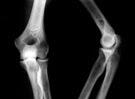

En el Hospital Universitario de Marburg y la Universidad de Ulm en Alemania se ha realizado un ensayo aleatorio controlado en el que se demuestra que el uso de pulsos de ultrasonidos de baja intensidad (PUBI) en pacientes con fracturas de tibia que mostraban una progresión pobre en su curación dio lugar a un aumento del 34 por ciento en la densidad mineral ósea en el área de la fractura después de 16 semanas en comparación con el uso de un dispositivo falso control. Estos resultados se publican en la revista Musculoskeletal Disorders.

Según explica Jon E. Block, director del estudio, estos descubrimientos demuestran un progreso superior hacia la curación ósea después del tratamiento con el ultrasonido en comparación con el tratamiento sin él en individuos con retrasos en la reunificación de la tibia. Esto debería ayudar a establecer una modalidad no invasiva como una opción de tratamiento eficaz y viable para los pacientes que sufren estas lesiones.

Los pacientes del estudio tenían toda una fisura en la tibia duradera que mostró una progresión mala en su curación.El aumento estimado en la densidad mineral ósea entre quienes siguieron el tratamiento con el dispositivo activo de ultrasonidos fue un 34 por ciento superior. Según concluye Block, este es el primer estudio que ofrece una evidencia de nivel 1 de este efecto en este tipo de fracturas.